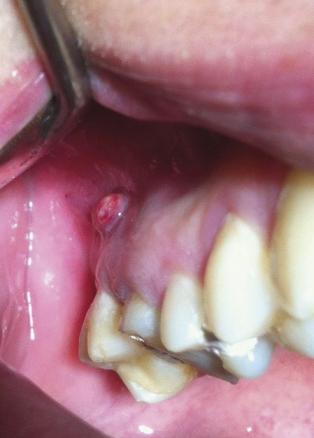

Louis, 20 ans, sans antécédent, se présente à sa visite médicale périodique. On découvre une protubérance gingivale inquiétante (photo 1 ) au niveau de la table osseuse externe de la dent n° 16. Fluctuante et régulière, elle ne saigne pas au contact.

La fistulisation survient au stade chronique de l’infection après des mois, voire des années, d’évolution. Elle peut se faire au niveau de la muqueuse (95 % des cas) ou de la peau. Le patient néglige le plus souvent la lésion, qui apparaît à distance de l’épisode aigu et est asymptomatique. Après avulsion de la dent en cause et curetage soigneux de la lésion infectieuse, le patient a bénéficié d’un traitement par bains de bouche et antibiotique (amoxicilline-acide clavulanique 1 g 3 fois par jour pendant 7 jours). L’évolution a été favorable. L’examen post-avulsionnel de la dent n° 16 (photo 3 ) a montré qu’une perforation instrumentale, lors d’un traitement radiculaire de la racine disto-vestibulaire, était à l’origine du foyer infectieux.